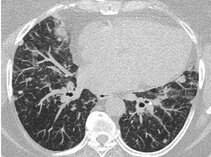

Granulomatous and Interstitial lung disease (ILD) affects about 15% of patients with common variable immunodeficiency (CVID) severely impacting their morbidity and mortality. So far only a few retrospective studies have evaluated this entity. The etiology, pathogenesis and risk factors contributing to the development of this inflammatory organ disease in CVID are not known. Viral triggers have been postulated but not confirmed in additional cohorts. The histological involvement of the pulmonary tissue varies and includes most often a mixed picture of granulomatous disease, lymphocytic interstitial pneumonitis (LIP), cryptic organizing pneumonia (COP) and follicular bronchiolitis and sometimes fibrosis presenting with diverse CT images. The prognosis of this manifestation varies widely. While severe cases progress to oxygen dependence within a few years, most patients have a milder course of disease. About 2/3 of patients require immunosuppressive therapy. Many case reports have suggested different therapeutic measures but no consensus has been reached on the best treatment beyond corticosteroids. In a large European multicenter study (STILPAD; Study of interstitial lung disease in primary antibody deficiency) 147 CVID patients of 14 centers are prospectively investigated, in order to answer some of the burning questions about pathogenesis, the natural course of the disease and optimal treatment strategies. eGLILDnet funded by the European Respiratory Society (ERS) has been founded in 2019 as a platform for exchange of physicians, researchers and patients on research, diagnostics and management of ILD in CVID. (1-12)